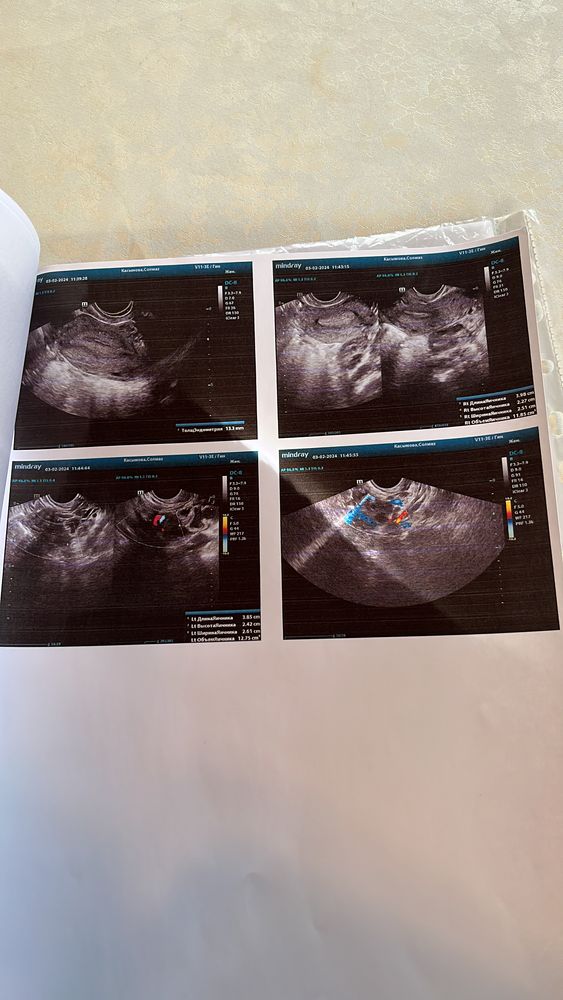

Почему нет желтого тела ?

Сходите в другое место, пусть посмотрят. Если есть жидкость, значит была... Эндометрий хороший, есть все шансы. Удачи😉

Мама девочки (9 лет), планирую беременность Уральск

Странное узи …. На 17 дц описывают что есть свободная жидкость, но!!!! Имеется «спавшийся»фолликул … это как ? Допустим, овуляция не наступила, потому что фолликул не дорос и «спал» Тогда откуда жидкость в позадиматочном пространстве ? Скорее всего ановуляторный цикл